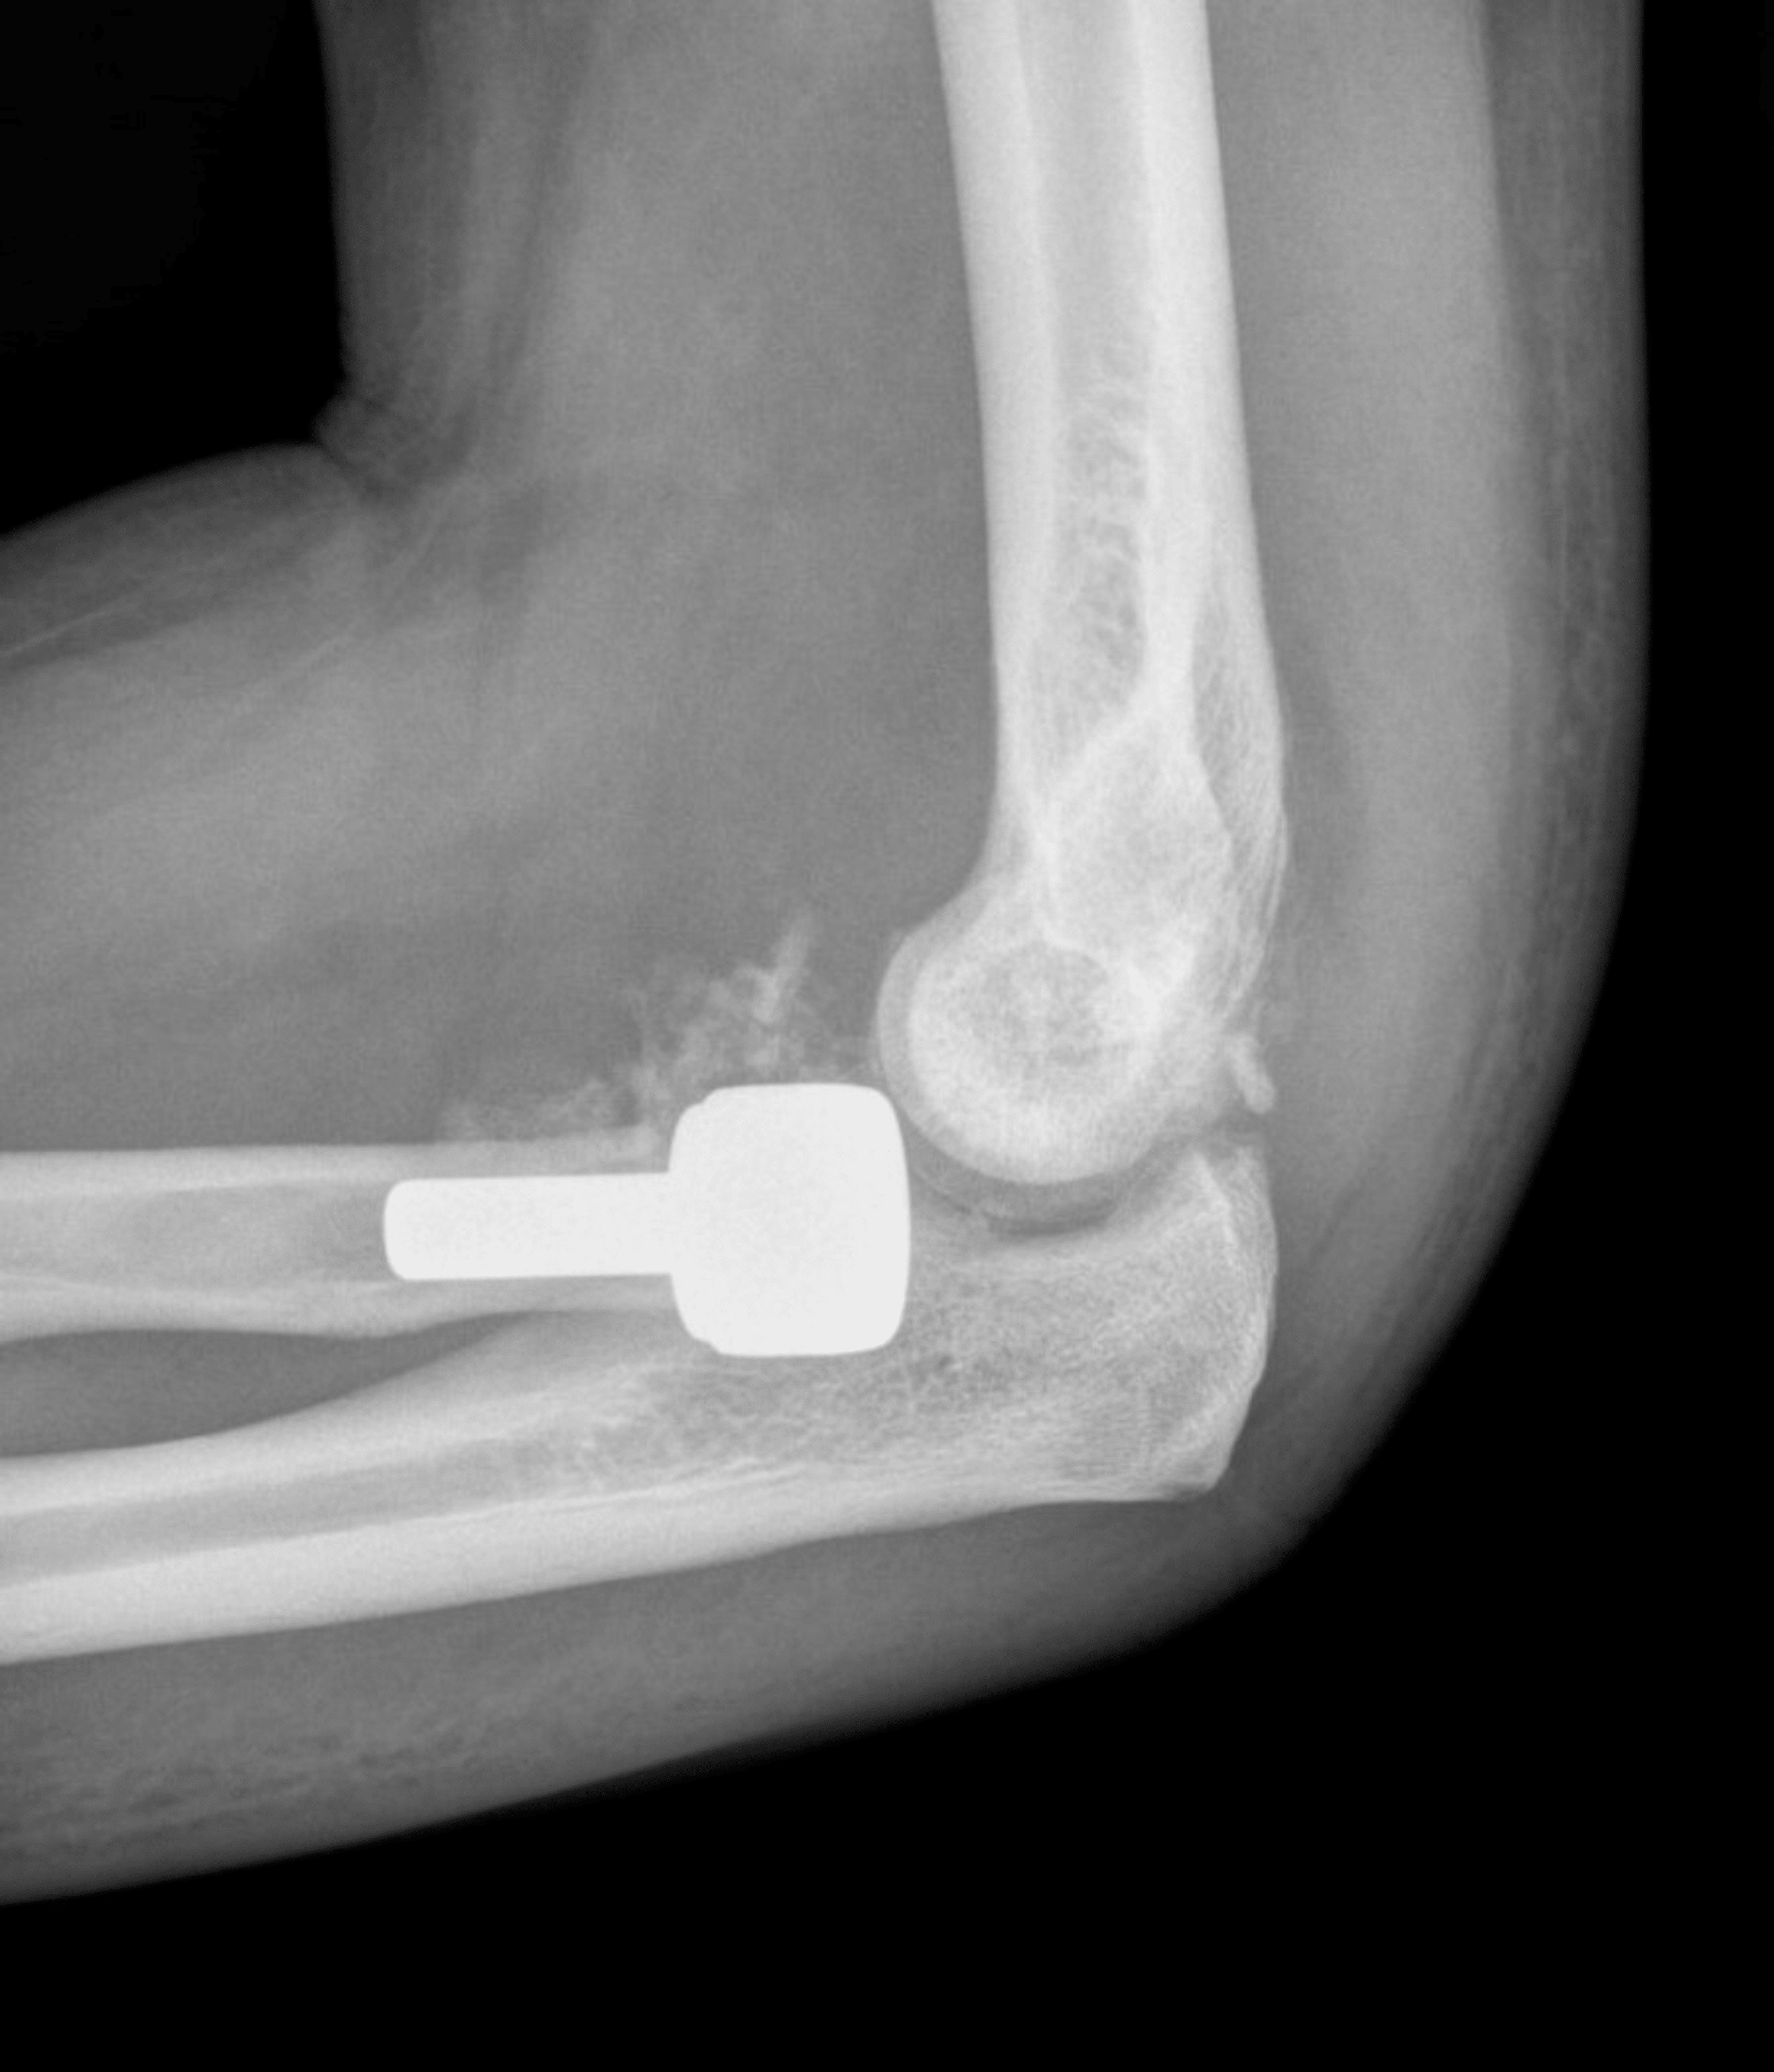

Surgical Implant Arm Elbow Xray Test Scan Stock Image - Image of elbows

Surgical Implant Arm Elbow Xray Test Scan Stock Image - Image of elbows of Panel For Elbow Reconstructive Surgery . Source: www.dreamstime.com